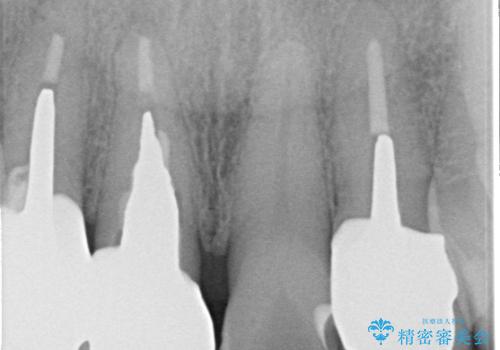

保険で治療した被せ物が劣化し色も変色をおこしていました。かつ被せ物と歯の境目(適合)も合っていない状態でした。

被せ物の適合が悪く劣化もおこし色が変色している状態でした。そのため他の歯とも色が合っていませんでした。古い被せ物を除去し形を整えた後にオールセラミッククラウンで治療を行いました。

根っこの先端に病巣(根尖性歯周炎)があったため根管治療または抜歯してインプラントを提案しましたが、患者さんのご希望により被せ物の治療のみを行いました。